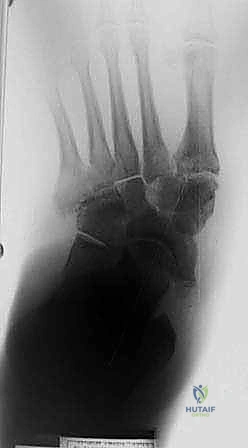

عملية تثبيت قدم شاركو (Charcot Foot Reconstruction) ليست جراحة عظام تقليدية؛ إنها إعادة هندسة كاملة لبنية القدم المنهارة. يتبع الأستاذ الدكتور محمد هطيف بروتوكولاً جراحياً دقيقاً يتضمن عدة مراحل:

الخطوة الأولى: التخطيط الجراحي الدقيق

قبل دخول غرفة العمليات، يتم إجراء فحوصات شاملة تشمل الأشعة السينية، الأشعة المقطعية ثلاثية الأبعاد (3D CT Scan) لفهم خريطة العظام المتفتتة، وتقييم شامل للدورة الدموية (Doppler Ultrasound) لضمان وصول دم كافٍ لالتئام الجروح.